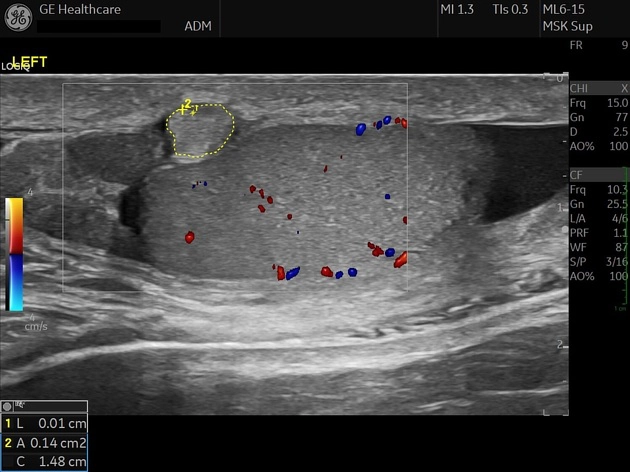

• Bìu và thừng tinh

• Khối u ở bìu